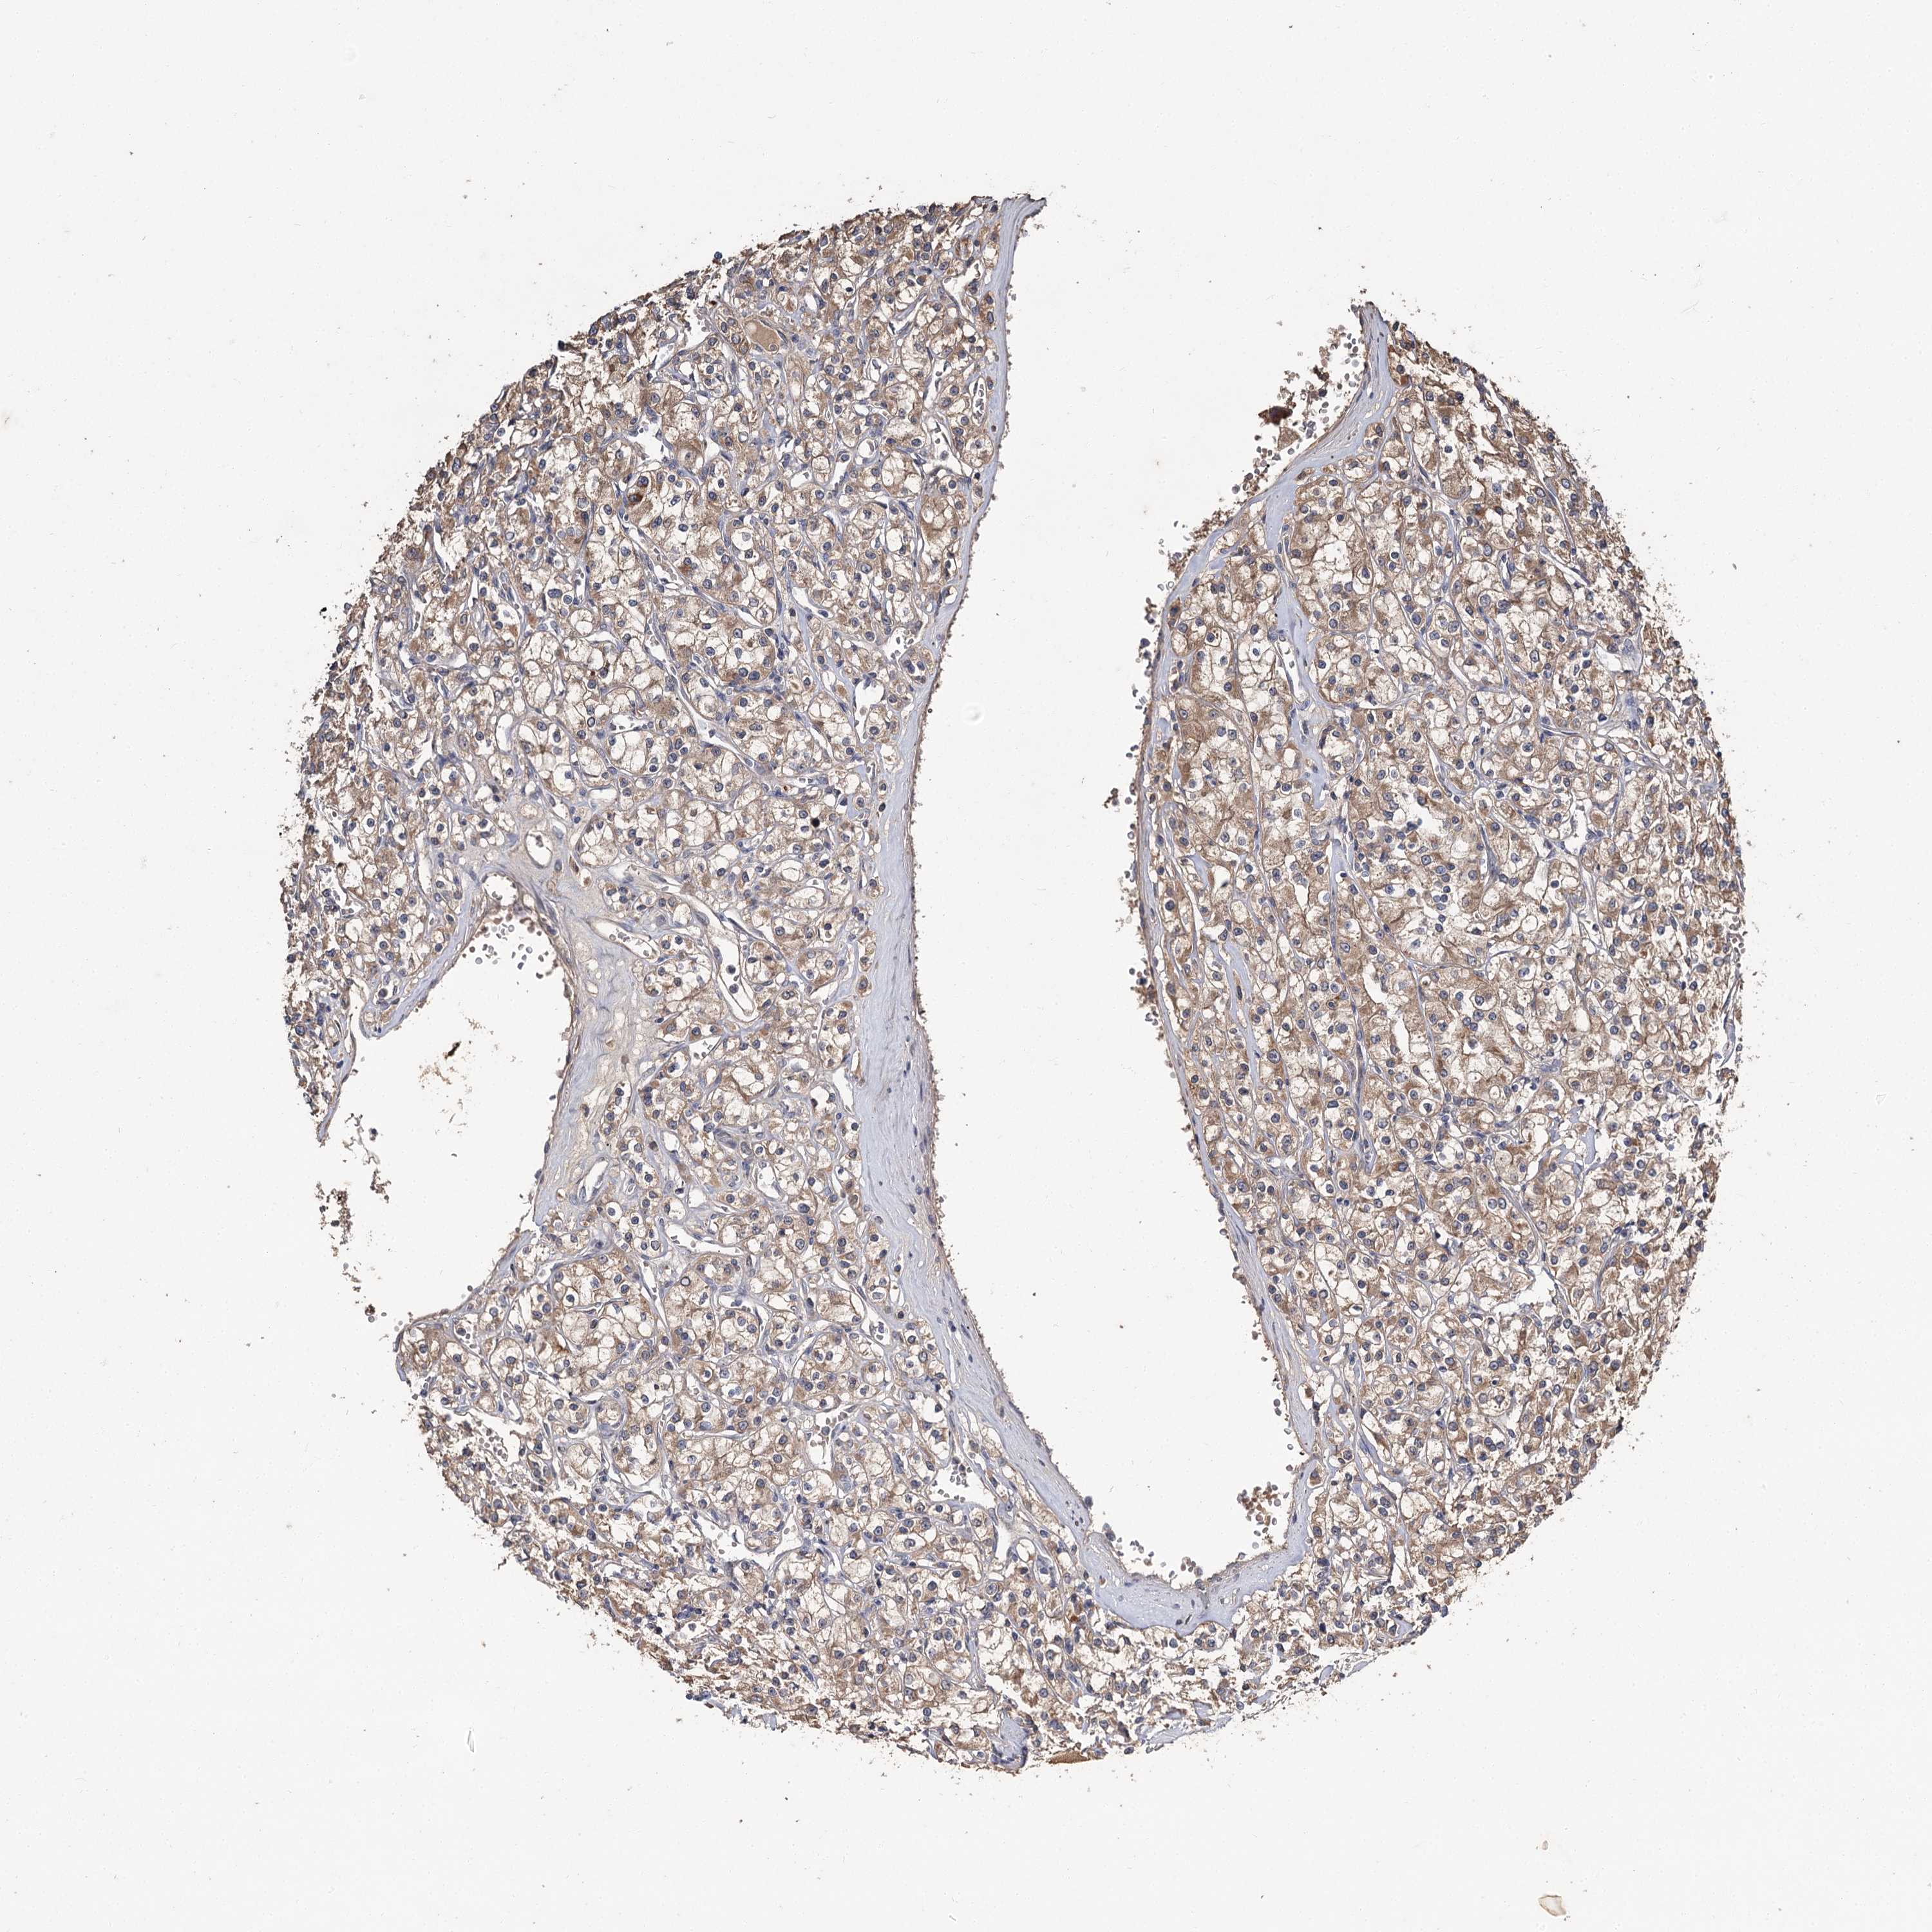

KIDNEY RENAL CLEAR CELL CARCINOMA (VALIDATION) - Interactive survival scatter ploti

The Survival Scatter plot shows the clinical status (i.e. dead or alive) for all individuals in the patient cohort, based on the same data that underlies the corresponding Kaplan-Meier plots. Patients that are alive at last time for follow-up are shown in blue and patients who have died during the study are shown in red.

The x-axis shows the expression levels (FPKM) of the investigated gene in the tumor tissue at the time of diagnosis. The y-axis shows the follow-up time after diagnosis (years). Both axes are complimented with kernel density curves demonstrating the data density over the axes. The top density plot shows the expression levels (FPKM) distribution among dead (red) and alive patients (blue). The right density plot shows the data density of the survived years of dead patients with high and low expression levels respectively, stratified using the cutoff indicated by the vertical dashed line through the Survival Scatter plot. This cutoff is automatically defined based on the FPKM cutoff that minimizes the p-score. The cutoff can be changed by dragging the vertical line or by entering a cutoff value in the square labeled "Current cut-off".

Under the Survival Scatter plot the p-score landscape (black curve; left axis) is shown together with dead median separation (red curve; right axis). Dead median separation is the difference in median mRNA expression between patients who have died with high and low expression, respectively. It is calculated as follows: median FPKM expression of dead patients with high expression - median FPKM expression of dead patients with low expression. This is intended to aid the user in visually exploring custom cutoffs and the associated p-scores and dead median separation.

Individual patient data is displayed and can be filtered by clicking on one or more of the category buttons on the top of the page. Categories describing expression level and patient information include: high, low, alive, dead, female, male and tumor stages. The scale of the x-axis can be toggled between linear and log-scale by clicking on the "x log" button. Mouse-over function shows TCGA ID, patient information and mRNA expression (FPKM) for each patient.

& Survival analysisi

Kaplan-Meier plots summarize results from analysis of correlation between mRNA expression level and patient survival. Patients were divided based on level of expression into one of the two groups "low" (under cut off) or "high" (over cut off). X-axis shows time for survival (years) and y-axis shows the probability of survival, where 1.0 corresponds to 100 percent.

MFN1 is not prognostic in Kidney Renal Clear Cell Carcinoma (validation)

Best expression cut offi

Based on the FPKM value of each gene, patients were classified into two groups and association between prognosis (survival) and gene expression (FPKM) was examined. The best expression cut-off refers the FPKM value that yields maximal difference with regard to survival between the two groups at the lowest log-rank P-value. Best expression cut-off was selected based on survival analysis .

When clicking on this number, the vertical dashed line indicating cut-off, the interactive survival plot, and the Kaplan-Meier curve will be adjusted to show results based on the best expression cut-off.

: 11.65

Median expressioni

Median expression refers to the median FPKM value calculated based on the gene expression (FPKM) data from all patients in this dataset. When clicking on this number, the vertical dashed line indicating cut-off, the interactive survival plot, and the Kaplan-Meier curve will be adjusted to show results based on the median expression.

: N/A

Median follow up timei

Median follow up time refers to the median time (years) after diagnosis with this type of cancer, based on clinical data from all patients in this dataset.

P scorei

Log-rank P value for Kaplan-Meier plot showing results from analysis of correlation between mRNA expression level and patient survival.

N/A

5-year survival highi

5-year survival for patients with higher expression than the expression cutoff.

For melanoma and glioma, 3-year survival is shown.

5-year survival lowi

5-year survival for patients with lower expression than the expression cutoff.

TCGA RNA samplesi

RNA-seq data is reported as average FPKM (number Fragments Per Kilobase of exon per Million reads), generated by the The Cancer Genome Atlas (TCGA) .

Normal distribution across the dataset is visualized with box plots, shown as median and 25th and 75th percentiles. Points are displayed as outliers if they are above or below 1.5 times the interquartile range. FPKM values of the individual samples are presented next to the box plot.

Average pTPM 11.8

Number of samples 100